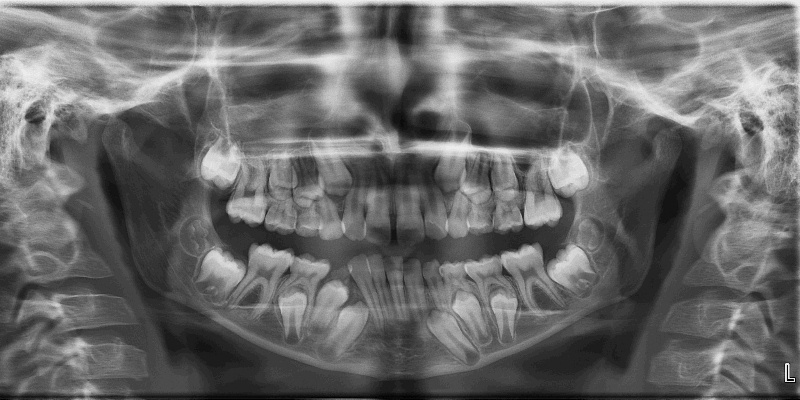

Dental Assistant Position in a Modern, Busy Dental Practice That Focuses on Excellent Patient Care is Available June 2025 will set up all the instrumentation involved in treating dental patients. After treatment has been completed, you will be responsible for cleaning the dental unit and sterilizing all instruments as well as setting the unit up for the next patient. The dental assistant is also responsible for digitally scanning the teeth, printing 3D models of the patient's teeth and taking dental X-rays-rays. You will also assist the doctor in providing patient care.

The Virginia Board of Dentistry regulates the standard of care delivered by dental assistants. Therefore, strict attention to details of this job is essential. You will be required to take a course on taking dental X-rays, and you must pass a certification examination following the course. The course is given at online from Laurel Ridge Community College and at other community colleges in the DC suburbs.